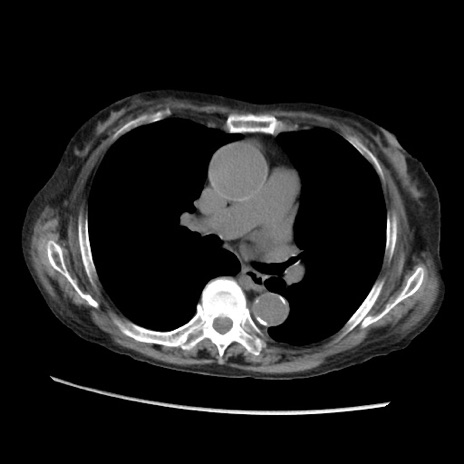

症例31(横断像)

【症例】80歳代 女性

【主訴】腹部膨満感

【現病歴】他院にて肝硬変にてフォロー中。1週間前から便秘、腹部膨満感、臍部腫瘤あり受診となる。

【既往歴】肝硬変

【身体所見】腹部膨隆あり、皮膚変化なし、疼痛なし。

【データ】WBC 4600、CRP 0.25